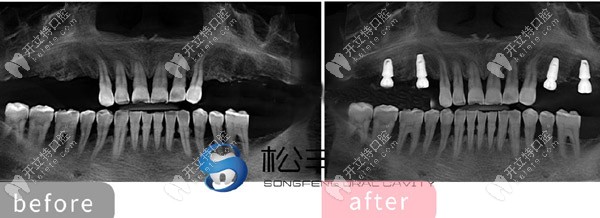

★ 顧客下頜多顆缺失,

上海松豐齒科的蔣院長(zhǎng)采用了即刻種植技術(shù),讓顧客當(dāng)天就了下半口牙。

下頜即刻種植